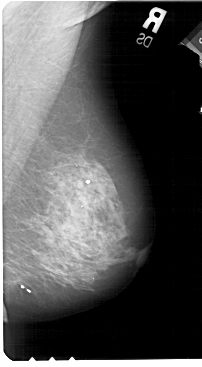

A_1488_1.LEFT_MLO

LEFT_MLO LINES 5491 PIXELS_PER_LINE 3136 BITS_PER_PIXEL 12 RESOLUTION 43.5 OVERLAY